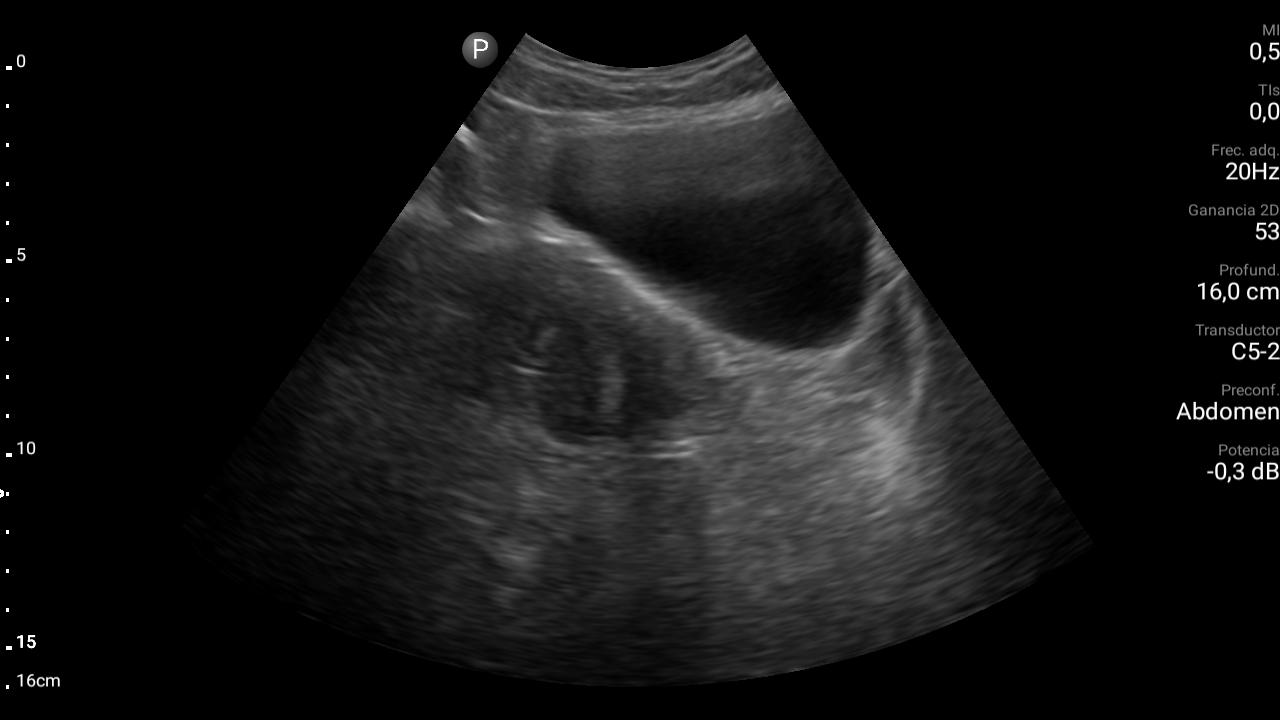

Hallazgos ecográficos

En ecografía abdominal se observa masa hipoecoica dependiente de útero por lo que se remite de forma preferente a ginecología.

En ginecología le realizan ecografía transvaginal, siendo diagnosticada de mioma uterino.